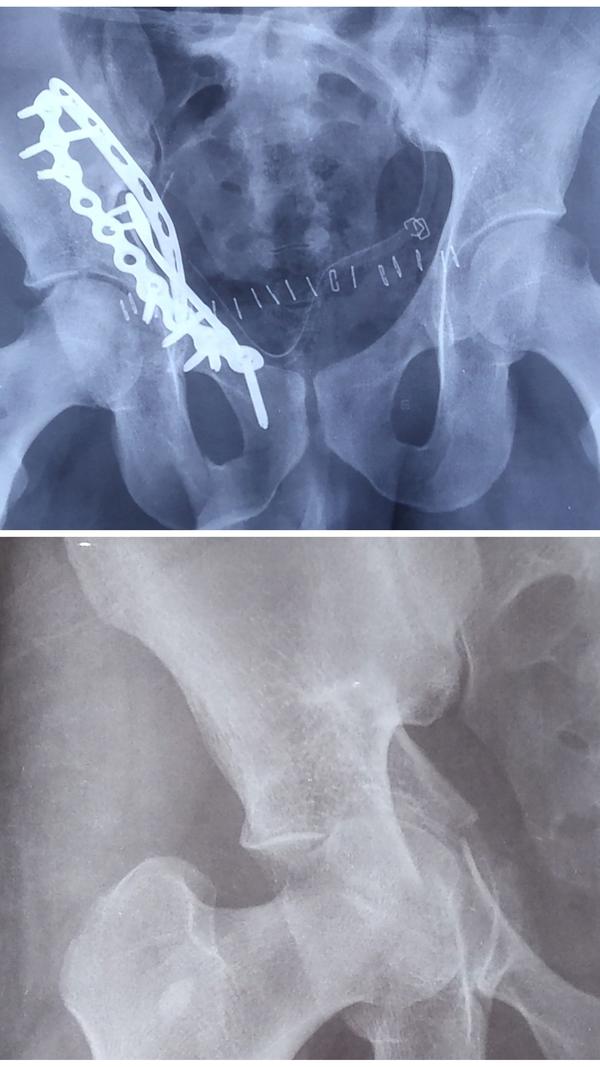

ACETABULUM/ PELVIC FRACTURE SURGERY IN GREATER NOIDA/NOIDA